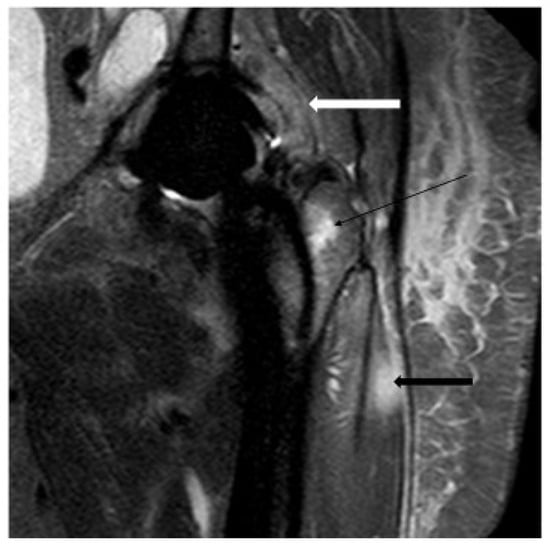

4.4. Magnetic Resonance Imaging

- Galley, J.; Sutter, R.; Stern, C.; Filli, L.; Rahm, S.; Pfirrmann, C.W. Diagnosis of periprosthetic hip joint infection using MRI with metal artifact reduction at 1.5 T. Radiology 2020, 296, 98–108. [Google Scholar] [CrossRef] [PubMed]

- Schwaiger, B.J.; Gassert, F.T.; Suren, C.; Gersing, A.S.; Haller, B.; Pfeiffer, D.; Dangelmaier-Dawirs, J.; Roski, F.; von Eisenhart-Rothe, R.; Prodinger, P.M. Diagnostic accuracy of MRI with metal artifact reduction for the detection of periprosthetic joint infection and aseptic loosening of total hip arthroplasty. Eur. J. Radiol. 2020, 131, 109253. [Google Scholar] [CrossRef]

- Inaoka, T.; Kitamura, N.; Sugeta, M.; Nakatsuka, T.; Ishikawa, R.; Kasuya, S.; Sugiura, Y.; Nakajima, A.; Nakagawa, K.; Terada, H. Diagnostic value of advanced metal artifact reduction magnetic resonance imaging for periprosthetic joint infection. J. Comput. Assist. Tomogr. 2022, 46, 455–463. [Google Scholar] [CrossRef]

- Plodkowski, A.J.; Hayter, C.L.; Miller, T.T.; Nguyen, J.T.; Potter, H.G. Lamellated hyperintense synovitis: Potential MR imaging sign of an infected knee arthroplasty. Radiology 2013, 266, 256–260. [Google Scholar] [CrossRef]

- Gao, Z.; Jin, Y.; Chen, X.; Dai, Z.; Qiang, S.; Guan, S.; Li, Q.; Huang, J.; Zheng, J. Diagnostic value of MRI lamellated hyperintense synovitis in periprosthetic infection of hip. Orthop. Surg. 2020, 12, 1941–1946. [Google Scholar] [CrossRef] [PubMed]

| Switzerland | 40/H | Periosteal reaction | MRI with metal artifact reduction | 78 | 90 | NA | NA | 86 | [69] |

| Switzerland | 40/H | Capsule edema | MRI with metal artifact reduction | 83 | 95 | NA | NA | 91 | [69] |

| Switzerland | 40/H | Intramuscular edema | MRI with metal artifact reduction | 95 | 86 | NA | NA | 89 | [69] |

| Germany | 41/H | Clinical and IO | MRI with metal artifact reduction | 86 | 73 | NA | NA | NA | [70] |

| China | 50/H | Lamellated hyperintense synovitis | MRI | 80–88 | 84–92 | 83–92 | 81–88 | NA | [75] |

| China | 56/H | Intraoperative findings with M and H | MRI | 94 | 97 | NA | NA | NA | [79] |